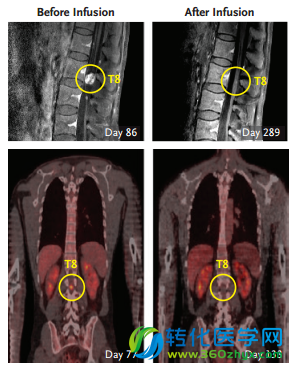

经过MRI和PET(正电子发射断层扫描,灵敏度和特异性更高,可在病变区的形态结构尚未呈现异常时就发现,还可鉴别肿瘤良恶性,并且可以全身成像)检查,都没有发现有肿瘤的迹象。而且患者在治疗中几乎没有出现什么严重的副作用,这一点也很重要,要知道,就是因为CAR-T疗法严重的神经毒性,导致JUNO公司CAR-T的II期临床试验中2名患者死亡,试验也曾短暂地被FDA叫停。

患者脊柱位置转移瘤在不同治疗时间的成像示意图

在此基础上,第二次治疗开始了,研究人员在右侧脑室进行了10次注射。注射进行了3次(实验的第133天)后,研究人员被一个喜讯“唤醒”——患者脑内和脊柱内的所有肿瘤都变小了!紧接着,在第5次注射(第190天)后,部分肿瘤消失了,剩下一部分减小了77%。在剩下的5次注射结束后,研究人员发现,患者体内的肿瘤全都消失了!